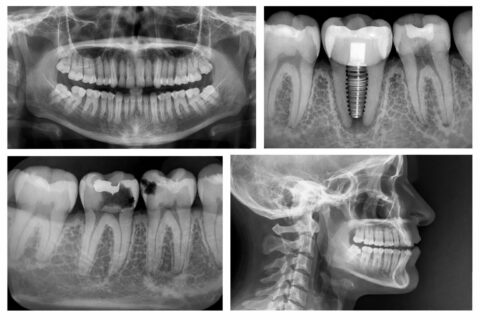

Digital dental radiography is a modern imaging technology used to capture highly detailed images of your teeth, gums, and jaw. Instead of traditional film, digital x-rays use a small electronic sensor that immediately sends images to a computer. This allows your dentist and hygienist to view, enlarge, and analyze the images in real time, making it easier to identify concerns quickly and accurately.

Compared to conventional film x-rays, digital systems significantly reduce radiation exposure — often by up to 80–90% — while still providing exceptional diagnostic detail.

Dental x-rays are a critical part of preventive and diagnostic care because they reveal areas that cannot be seen during a visual exam alone. These images help your dental team detect issues early and develop a precise treatment plan. Without x-rays, many dental problems could progress unnoticed.

Dental x-rays can help identify:

• Infections such as abscesses or cysts

• Bone loss related to gum disease

• Benign or malignant growths

• Cavities between teeth

• Developmental concerns

• Misaligned teeth or root positioning issues

• Problems within the tooth or beneath the gum tissue